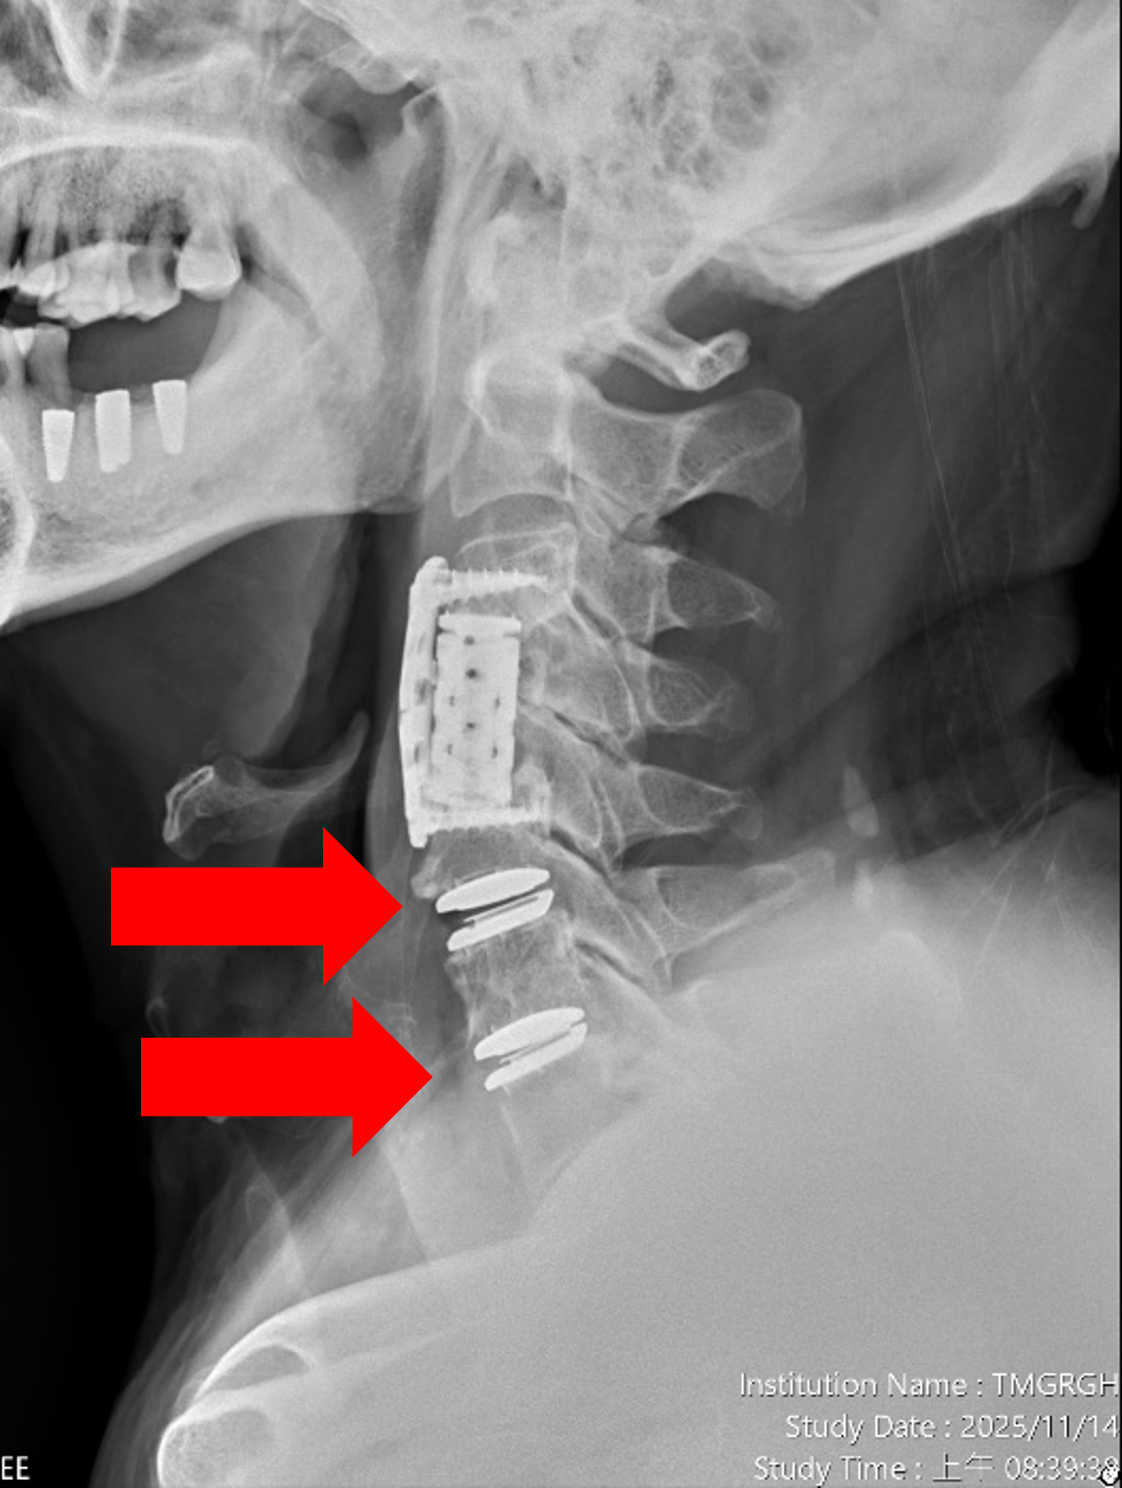

圖四、【治療後】患者的第五第六及第六第七頸椎間盤切除,並植入人工椎間盤,患者術後症狀解除,不需戴頸圈,一個星期就能回工作崗位。